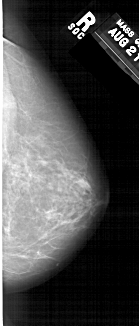

A_1370_1.RIGHT_MLO

RIGHT_CC LINES 6181 PIXELS_PER_LINE 2641 BITS_PER_PIXEL 12 RESOLUTION 43.5 NON_OVERLAY

FILE: A_1370_1.LEFT_CC.OVERLAY

TOTAL_ABNORMALITIES 1

ABNORMALITY 1

LESION_TYPE MASS SHAPE IRREGULAR MARGINS ILL_DEFINED

ASSESSMENT 4

SUBTLETY 3

PATHOLOGY BENIGN

TOTAL_OUTLINES 1

BOUNDARY